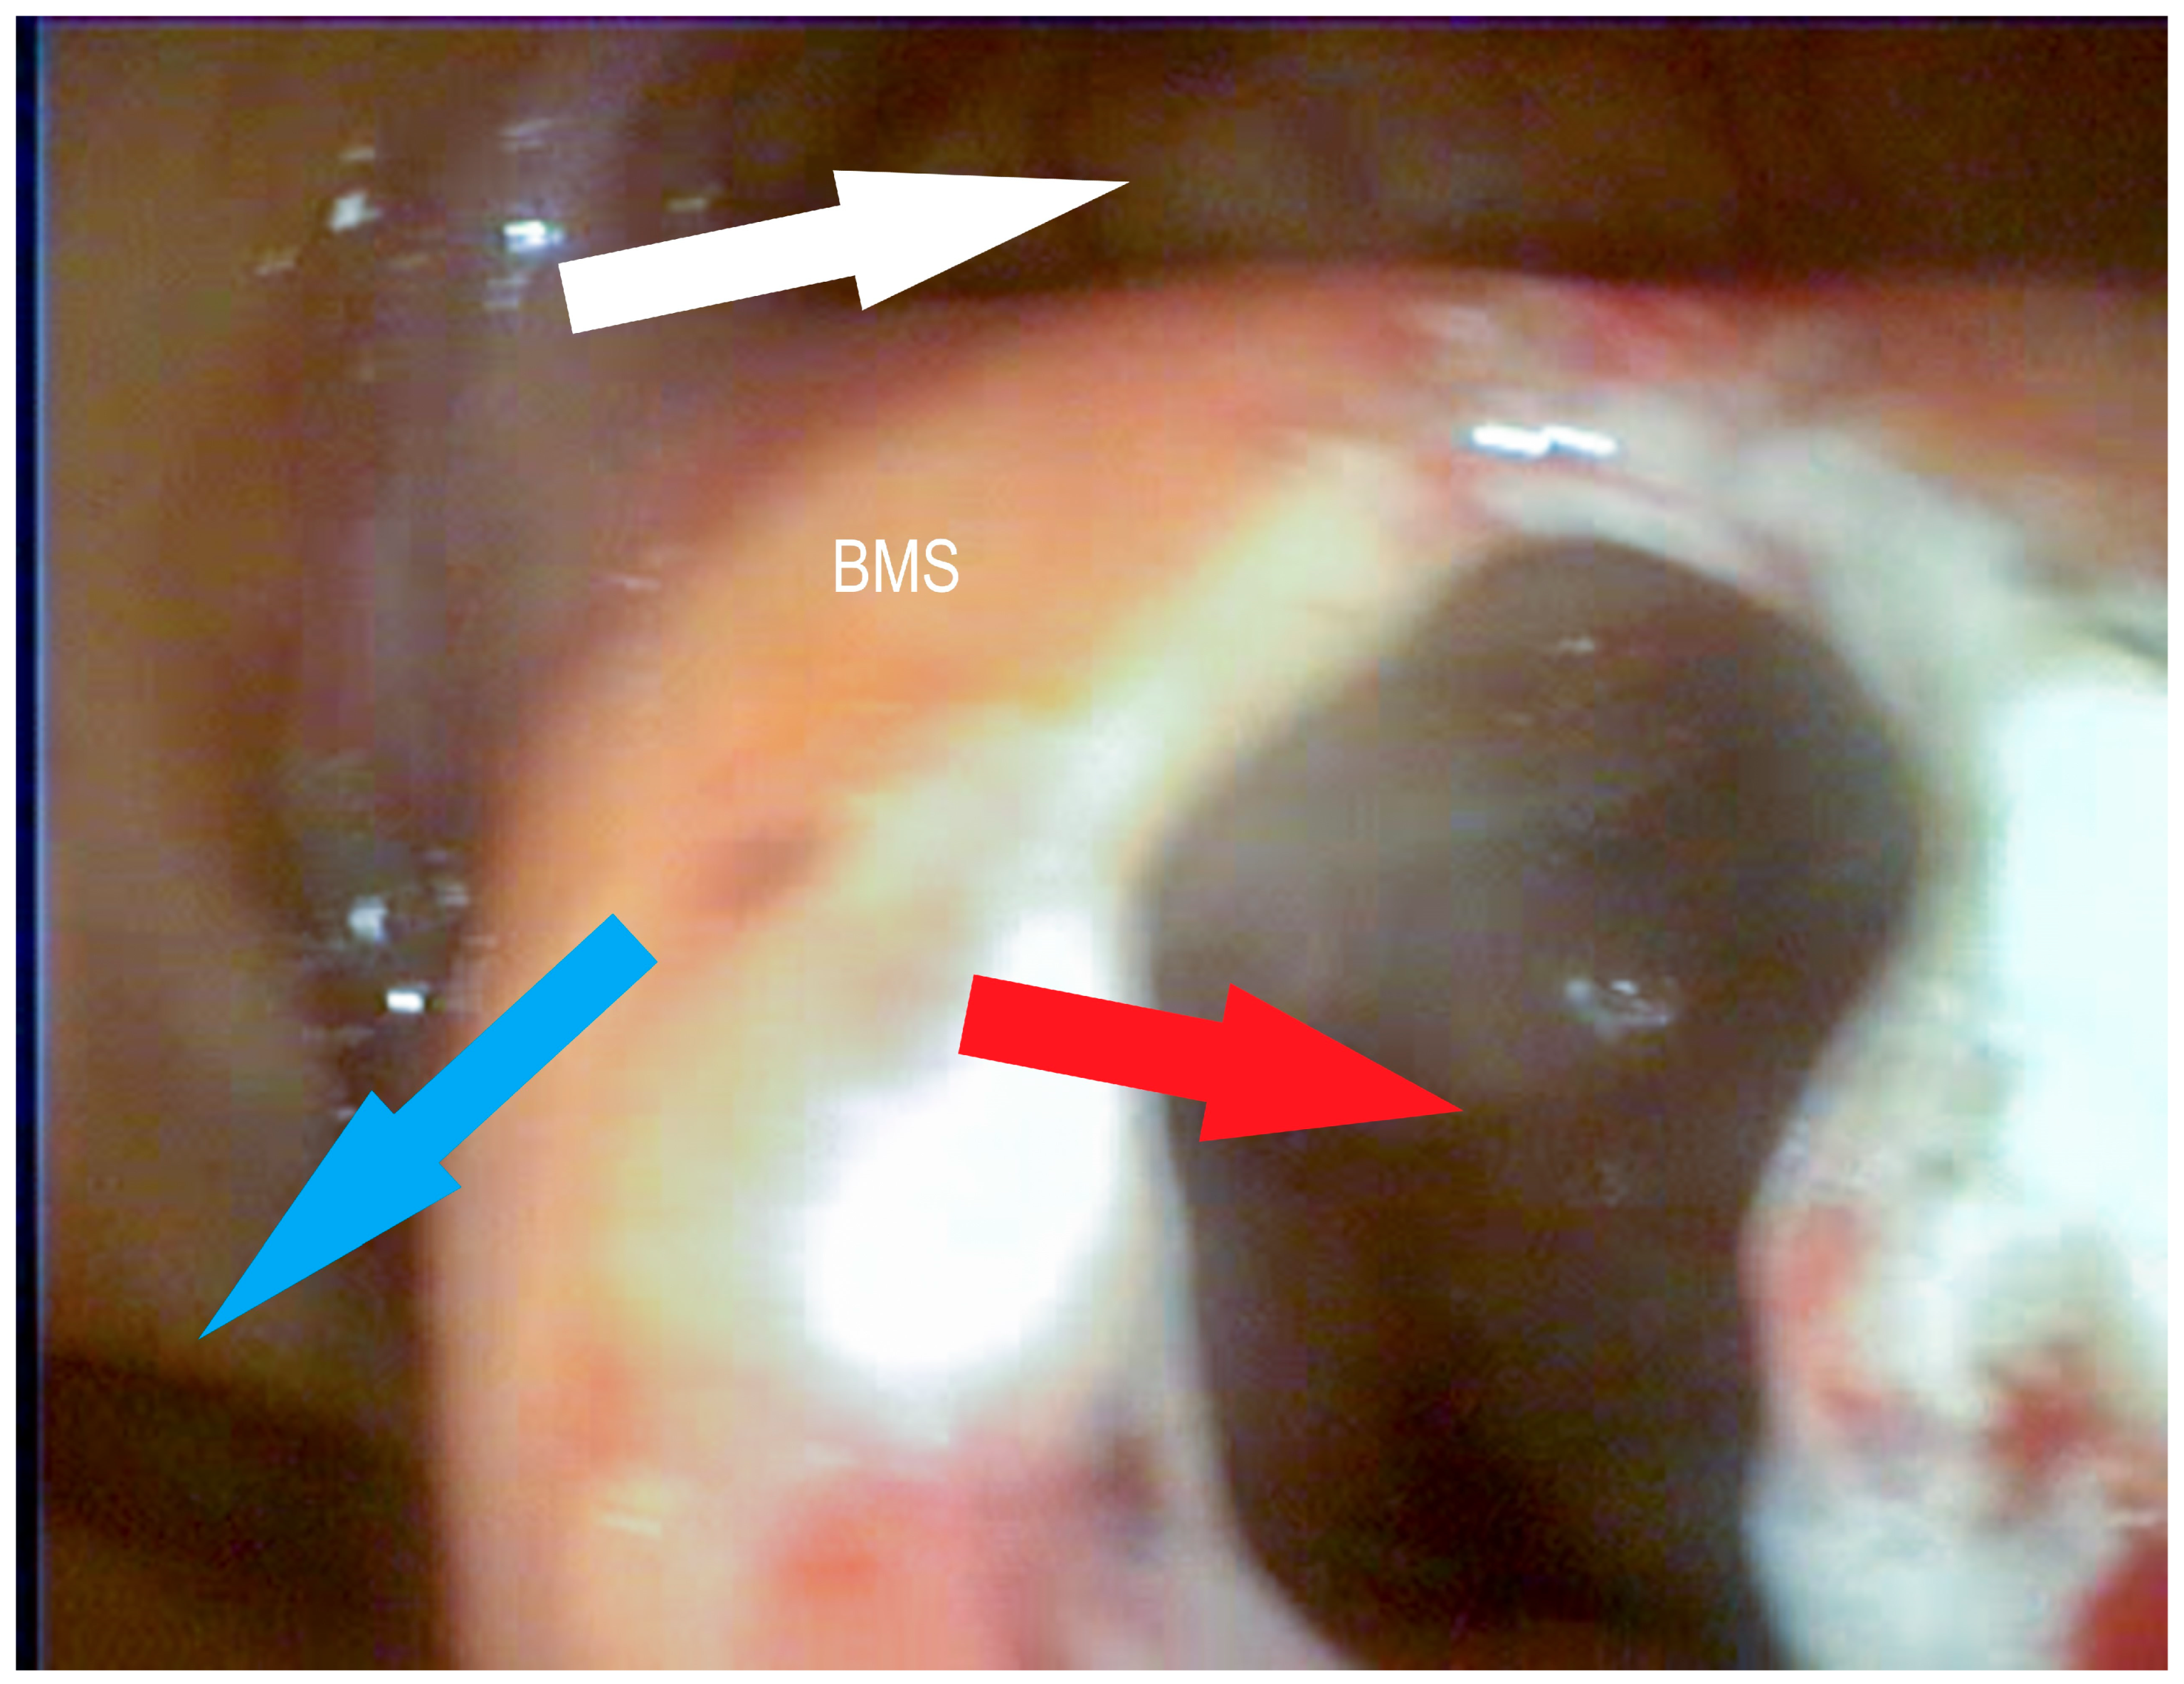

2.2.6. Transendoscopic Fenestration of the Bulla of the Maxillary Septum (BMS)

3.1.3. Conchotomy and Transendoscopic Laser Fenestration of the Bulla of the Maxillary Septum